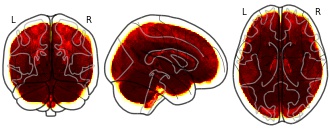

License information was derived automaticallyDescriptionAfter subtracting relevance maps per participant in the two MRI sequences (T1-FLAIR) from each other, 1-sample t-tests were computed to find areas which showed significant differences between the modalities.

Collection description

Brain-age (BA) estimates based on deep learning are increasingly used as neuroimaging biomarker for brain health; however, the underlying neural features have remained unclear. We combined ensembles of convolutional neural networks with Layer-wise Relevance Propagation (LRP) to detect which brain features contribute to BA. Trained on magnetic resonance imaging (MRI) data of a population-based study (n=2637, 18-82 years), our models estimated age accurately based on single and multiple modalities, regionally restricted and whole-brain images (mean absolute errors 3.37-3.86 years). We find that BA estimates capture aging at both small and large-scale changes, revealing gross enlargements of ventricles and subarachnoid spaces, as well as white matter lesions, and atrophies that appear throughout the brain. Divergence from expected aging reflected cardiovascular risk factors and accelerated aging was more pronounced in the frontal lobe. Applying LRP, our study demonstrates how superior deep learning models detect brain-aging in healthy and at-risk individuals throughout adulthood.

This collection contains statistical maps from the analysis of the above mentioned LRP relevance maps.